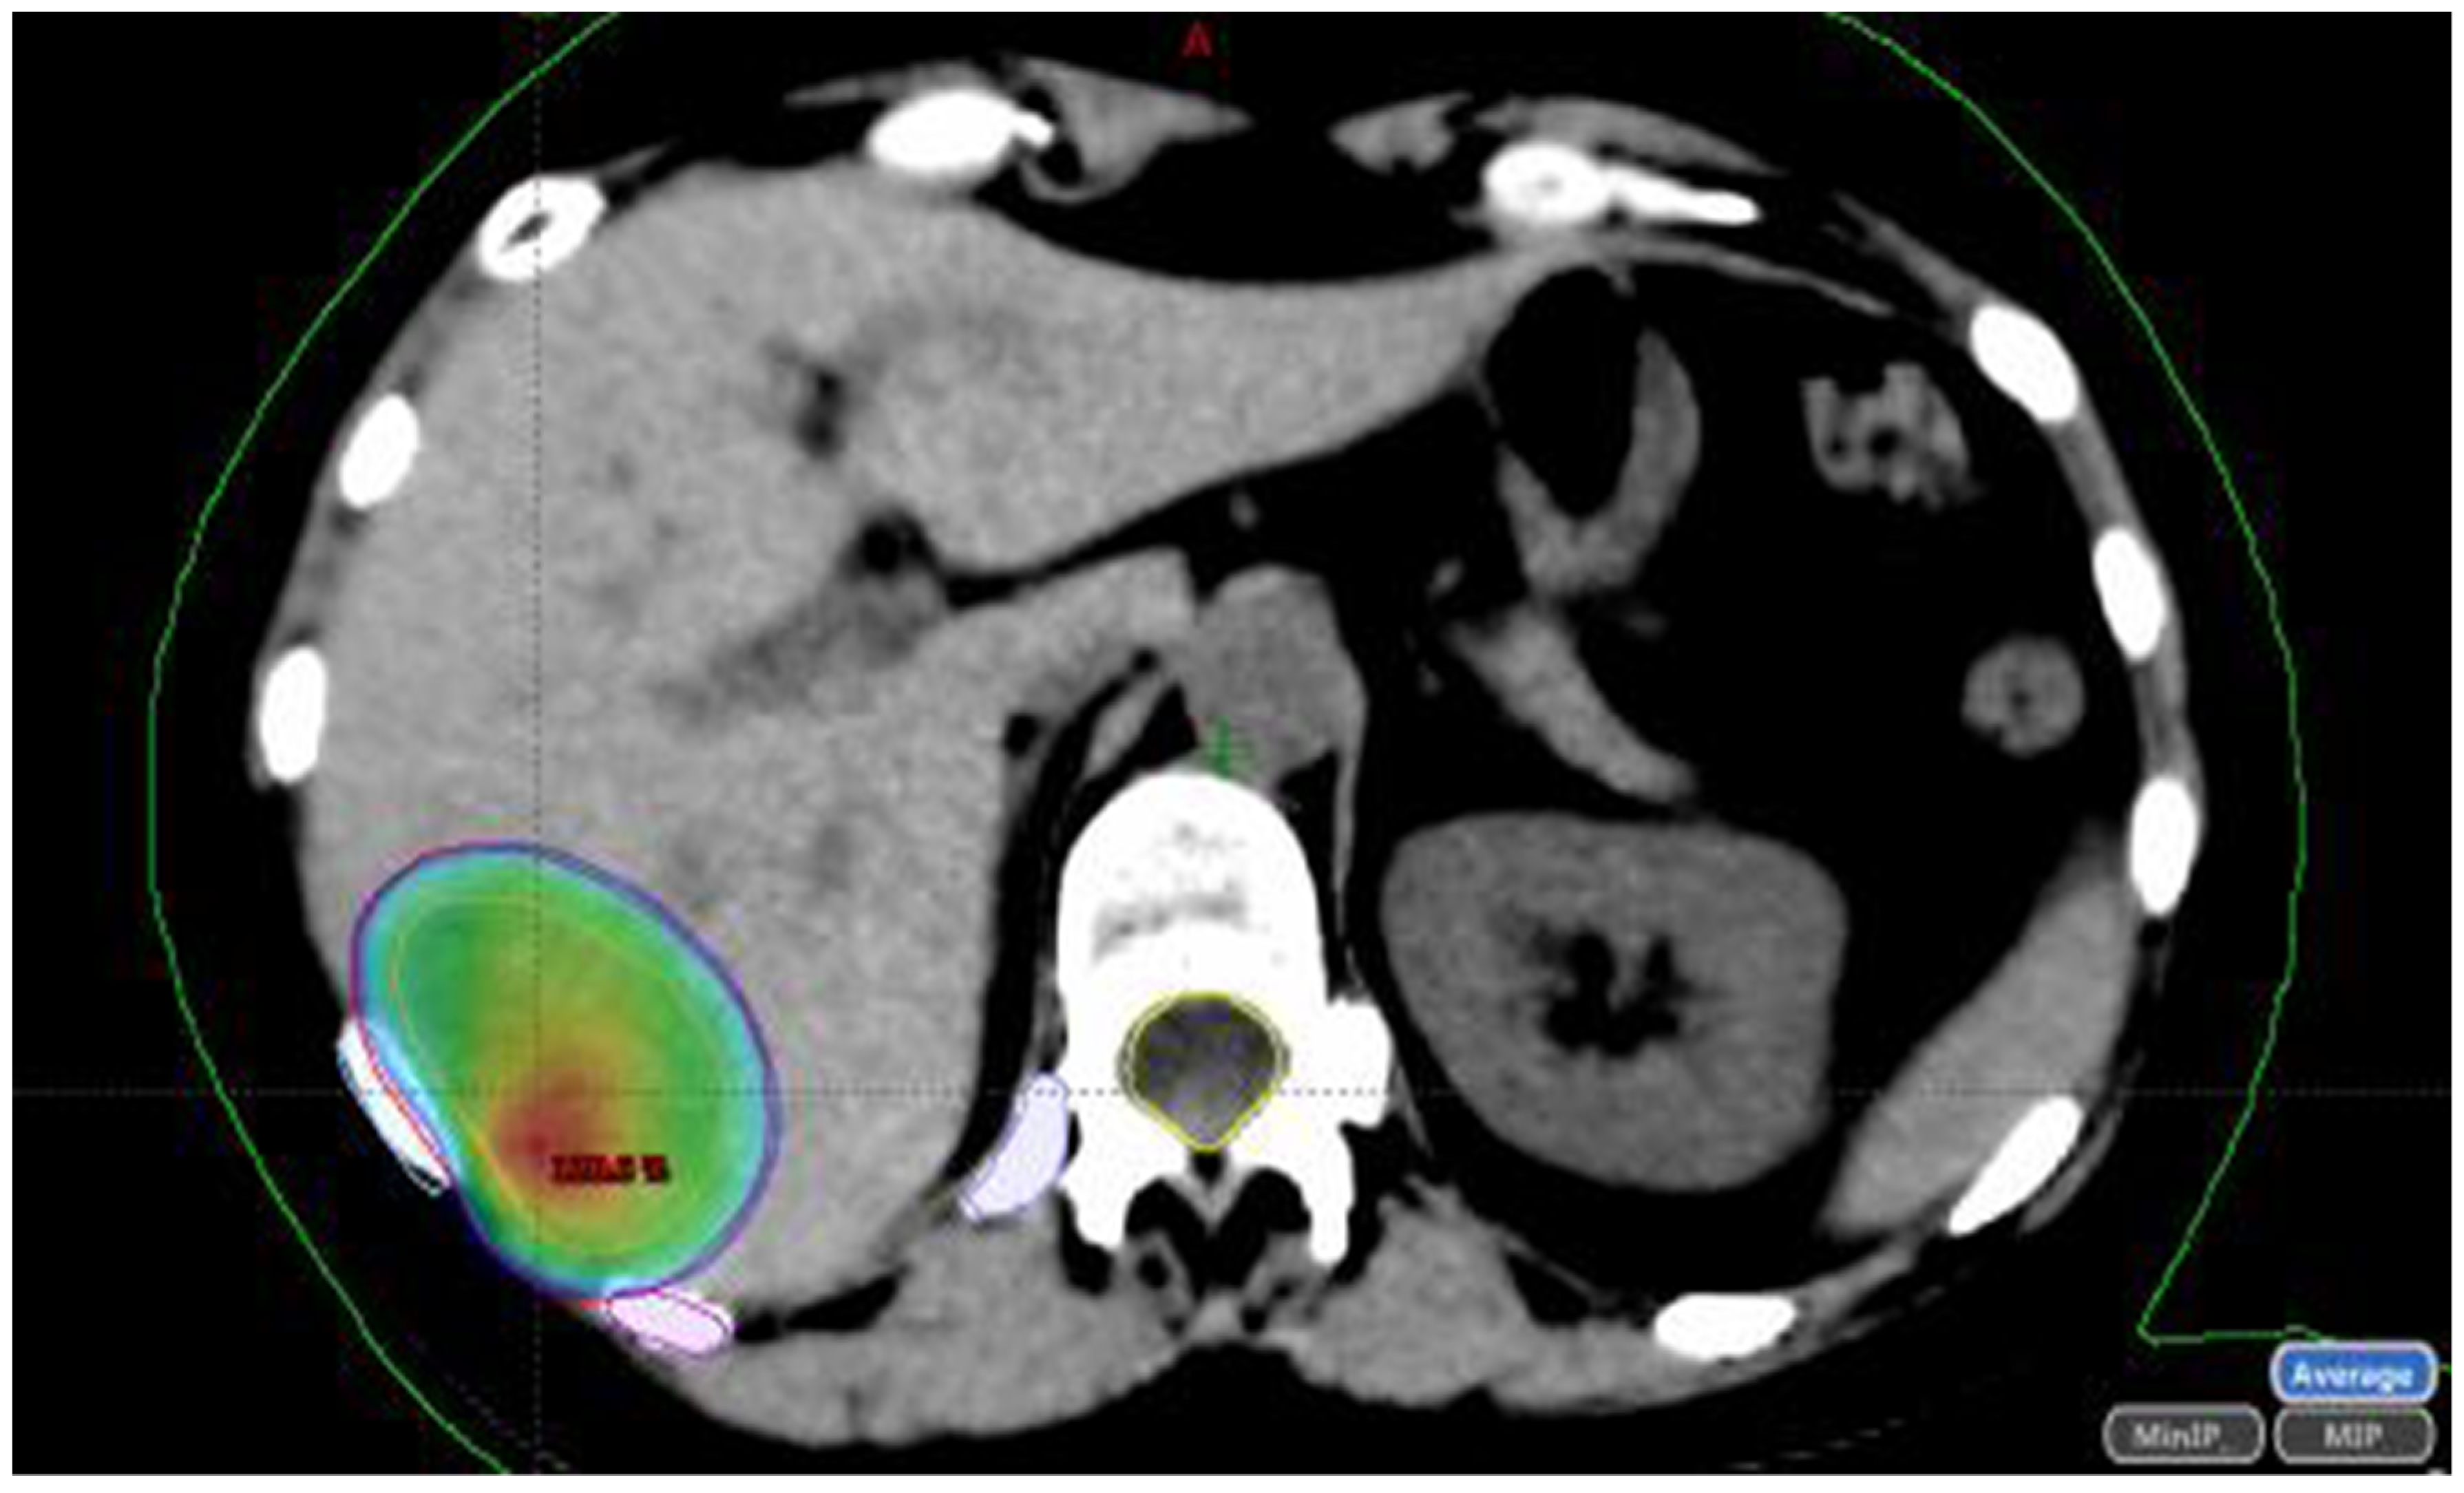

1.2. Stereotactic Body Radiotherapy (SBRT)

1.2.1. SBRT Technique

1.2.2. SBRT Dose

1.2.3. Criteria for Determining SBRT Suitability

1.2.4. SBRT Outcomes